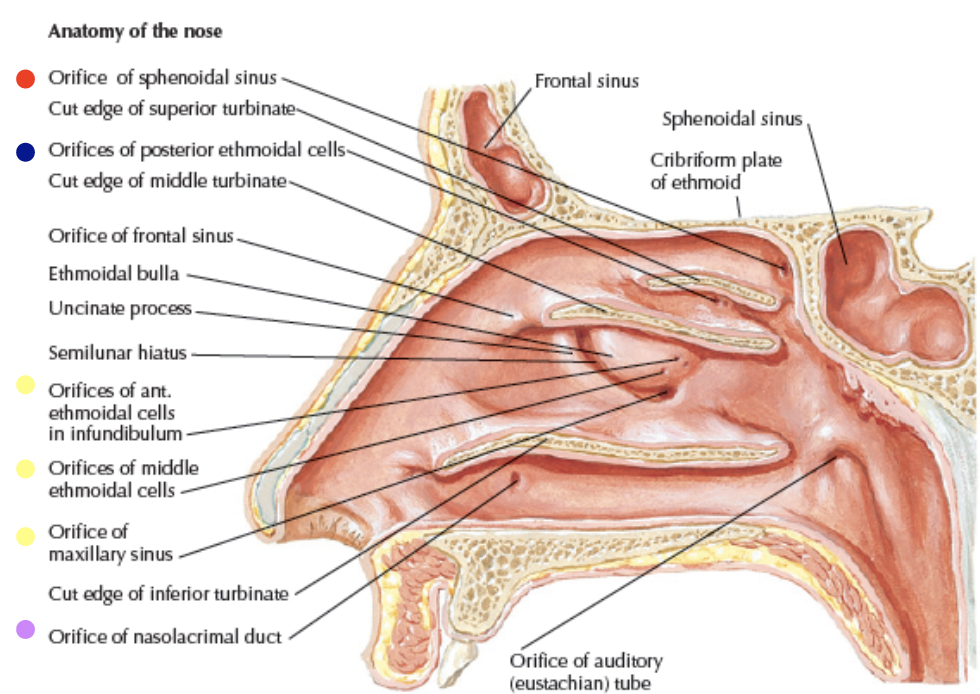

Nose cavity

Hypophyseal fossa

腦下垂體在這

Nasal septum (鼻中膈)

- nasal sepal cartilage

- perpendicular plate of ethmoid

- vomer

Nerve

- Olfactory n. (CN I)

- Anterior ethmoid n.

- 中下鼻甲前測一般感覺

-

Infraorbital n.

-

- Post. inf. nasal Br. of Greater palatine n.

- Nasopalatine n.

- 走在鼻中隔

- 穿過 Incisive canal

- Post. lat./med. sup. nasal n.

Artery

-

- 供應鼻中隔

-

- Septal br.

- Septal br.

-

- Sphenopalatine a.

- to Incisive canal

- Greater palatine a.

- Sphenopalatine a.

Paranasal sinuses

鼻旁竇,濕潤呼吸的空氣

Frontal sinus

神經皆CN V1

- Anterior ethmoid a.

- Supraorbital a./n.

- Supratrochlear (滑車上) a./n.

Maxillary sinus

來自Maxillary a. 3rd Part, Maxillary division

- Ant./mid. sup. alveolar a./n.

- Post. sup. alveolar a./n.

Ethmoid sinus

ethmoid bulla

Mid. ethmoid sinus 開口

Sphenoid sinus